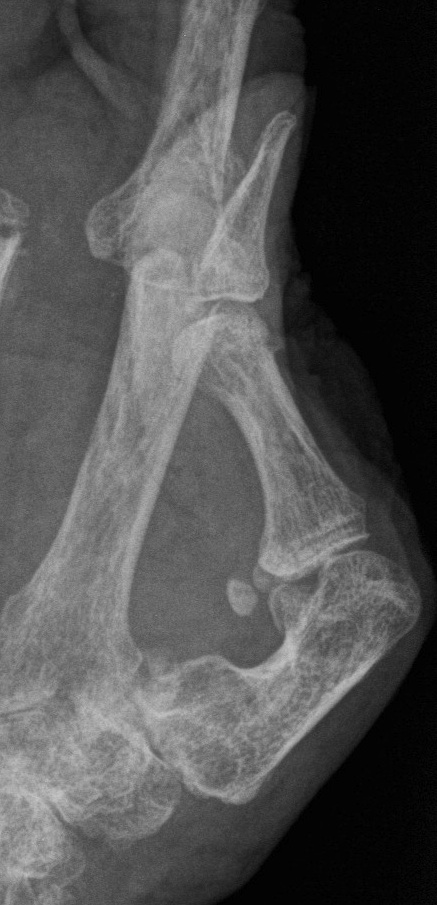

Muller-Weiss disease

Definition

Spontaneous osteonecrosis of the navicular